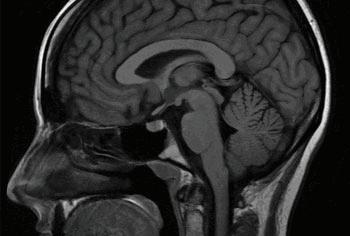

8 1 The Triune Brain Theory This is a model for the evolution of the vertebrate forebrain and behavior. The American physician and neuroscientist Paul D. MacLean proposed the theory that essentially three main parts of the brain control and regulate behavior as well as daily bodily functions, all of which are geared towards the body’s survival.

• The Brain Stem - The brain stem (or brainstem) regulates cardiac and respiratory functions for the body as well as the central nervous system. This central nervous system key to maintaining consciousness, regulation of sleep, heart rate, breathing, blinking, and eating (also known as circadian rhythms).

• The Cerebellum - The cerebellum is Latin for “little brain” that is responsible for coordination, balance, and gross motor control.

• The Cerebrum - The cerebrum is Latin for “brain” and it is the newest (evolutionarily) and largest part of the brain. It is where thought, decision-making, perception, judgment, and imagination occurs.

HTMBPR Figure 8.1 The Triune Brain (Cerebrum, Cerebellum, and The Brain Stem)